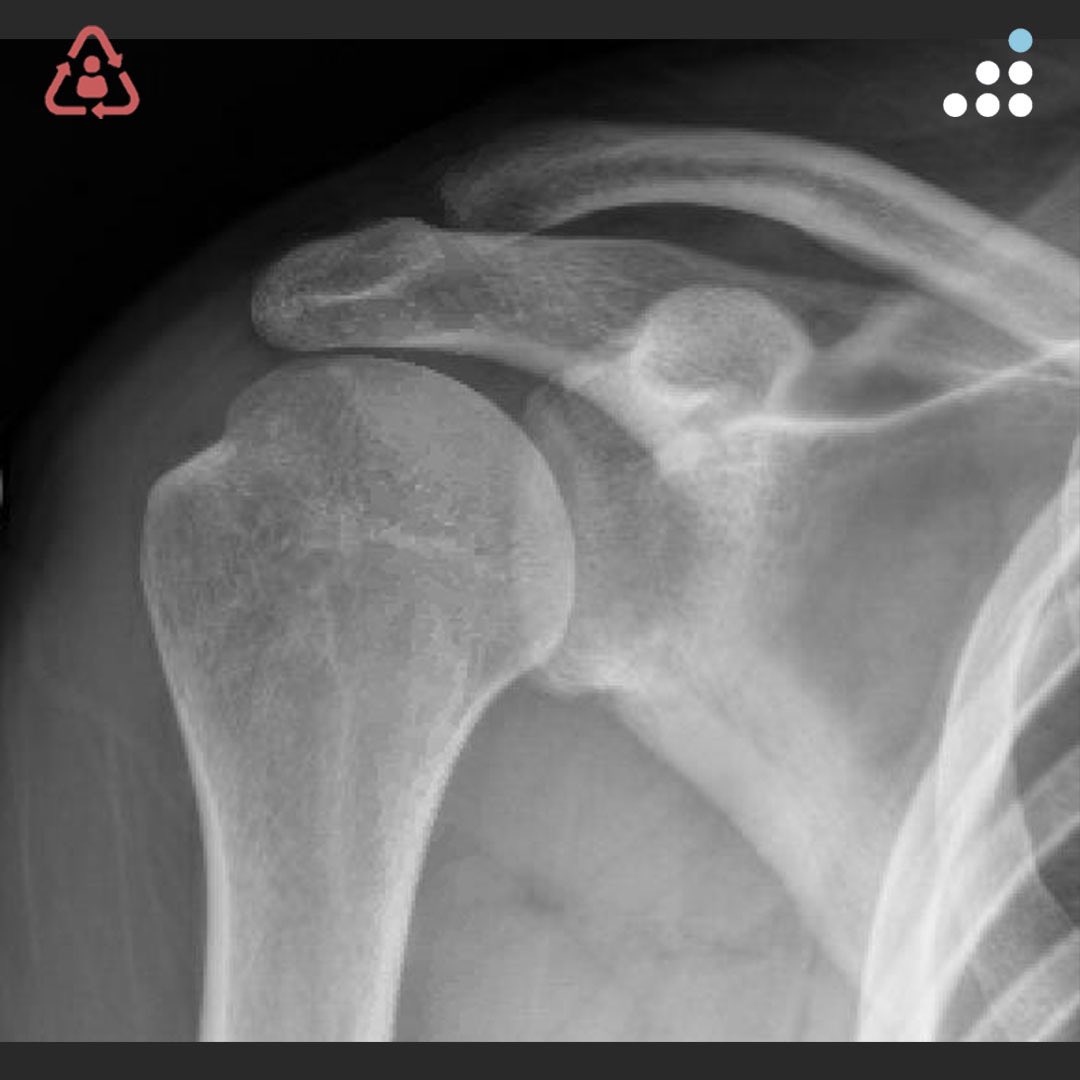

@orthobullets If there is still some cartilage left on the reverse Hill Sachs I’ve had some luck with doing a humeral head osteoplasty. I’ll use allograft chips or cement to backfill the defect after I tamp up articular surface and then try to get everything repaired especially in young pts